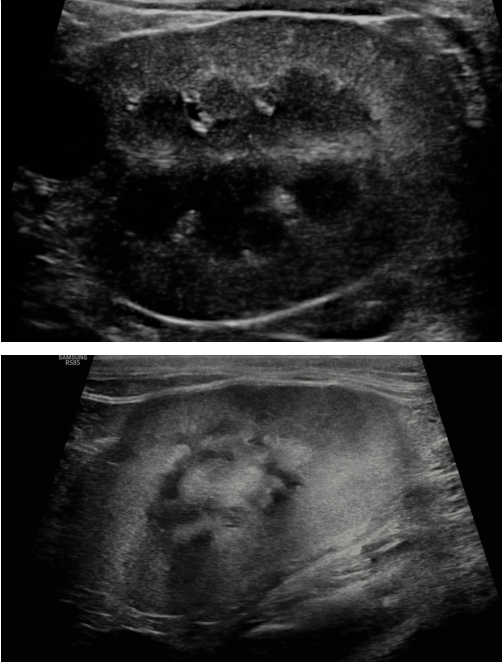

Imaging

- 칼슘이 과도하게 빠져나가는 이상이

- 전체적으로 뼈 밀도 감소 양상

- 영구 조직 mineralization

- 초음파만으로는 1/2기 구분 어려움